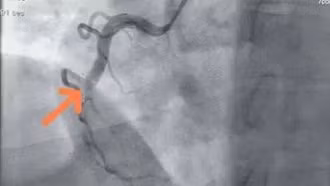

Đặt stent mạch vành giúp mở rộng lòng mạch tắc hẹp nhưng không thể phòng tránh nhồi máu cơ tim xảy ra ở những đoạn mạch bị tổn thương khác.